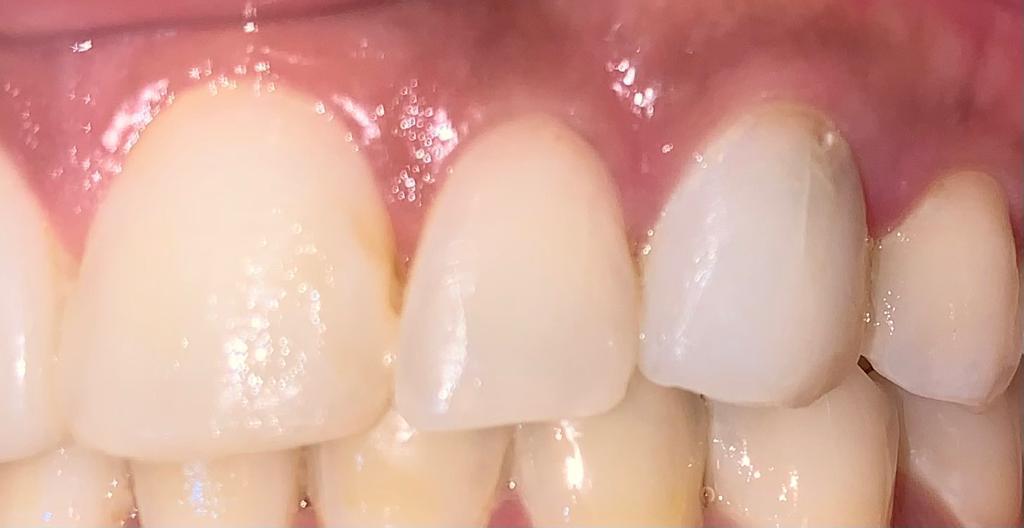

Antes de tratamiento con carillas dentales

Antes

Carillas - Situación Inicial

Estado inicial antes de aplicar nuestro tratamiento con carillas dentales para mejorar la estética.

Después de tratamiento con carillas dentales

Después

Carillas - Resultado

El resultado final de nuestro tratamiento con carillas dentales muestra una sonrisa perfecta y natural.